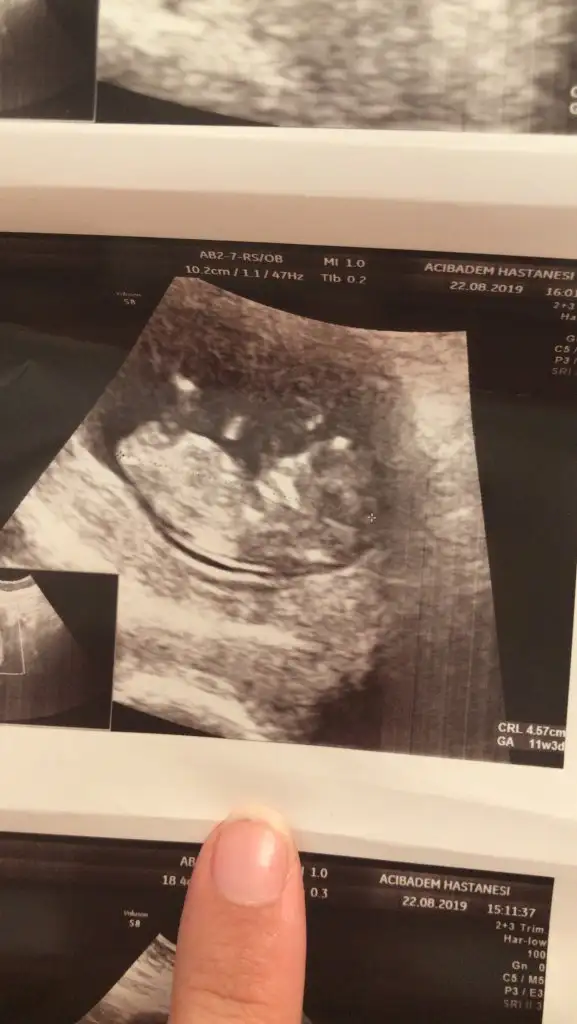

Cinsiyet tahmininde bulunsana

Bebek tam ortada canım bilemicem .biliyorsun senin kızı 11+3 haftasında tahminim tutmuştu.sende dr erken tahmin etti kıza benzetti demiştinHavalianne__ cinsiyetini tahmin edermisin

Net olmamakla birlikte kız başka usg varsa paylaşın

Bunda hic belli değil bence ama birde bu var :) yinede tesekkur ederimNet olmamakla birlikte kız başka usg varsa paylaşın

KızBunda hic belli değil bence ama birde bu var :) yinede tesekkur ederim